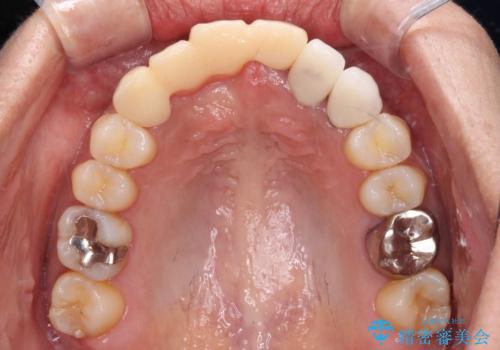

- 前歯を2本抜歯した後に装着した仮歯が長く見えるのが気になるとのことで来院された患者様です。

抜歯後には歯を支えていた骨が失われるため、歯肉が痩せてしまい、結果としてブリッジのダミーの歯を長くする必要があります。

前医では、歯肉の位置に相当する部分を、歯肉に近い色とすることで歯の長さが揃っているようにカムフラージュする治療が提案され、仮歯もそのようになっていました。

歯肉が痩せてしまっている状態を改善するため、口蓋から歯肉の結合組織を採取し、移植することで厚みを増大させることとし、その後オールセラミックブリッジにて補綴治療を行うこととしました。